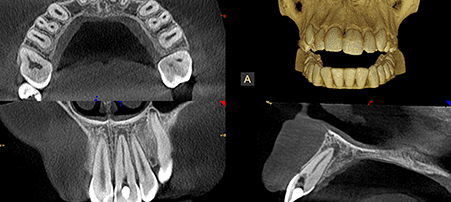

CBCT 3D Scanner

A state of the art scanning machine used to produce incredibly accurate and detailed 3D images. From single teeth to both upper and lower jaws in a single scan with a reduced radiation dose and high speed.

Extremely beneficial in detecting and diagnosing oral health problems and as an aid to planning of treatment. CBCT 3D Scanners are becoming extremely important as dentistry moves further into the digital generation.

- Complex Endodontic cases